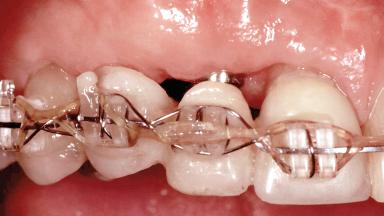

In 2001, a 48-year-old woman presented at a dental clinic with a failing fixed partial denture spanning from teeth 13 to 21. She was experiencing pain upon function, tenderness to palpation facial to tooth 13, and severe mobility of the prosthesis. Radiographic and clinical assessment revealed a subcrestal fracture of tooth 13, making its restoration unlikely. It was determined by the clinician that the tooth needed to be extracted prior to proceeding any further with dental care. After the extraction, the patient lost confidence in the progression of her treatment and sought consultation at the Center for Implant Dentistry. At her consultation visit in our clinic, an extra- and intraoral clinical examination revealed a medium lip line at full smile and an edentulous area spanning from 13 to 12 with both vertical and horizontal deficits in hard and soft tissue.

Soft Tissue Grafting Staged

Interim Prosthesis during Healing Fixed Fixed